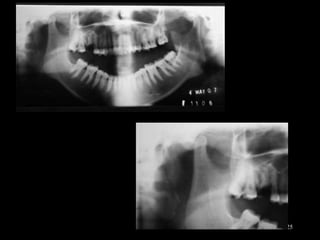

History

Determine cause & onset.

A prior h/o local joint laxity, ID, & other TMJD

use of antipsychotic drugs

physical examination

Neurological and musculoskeletal disorders

Radiological examination